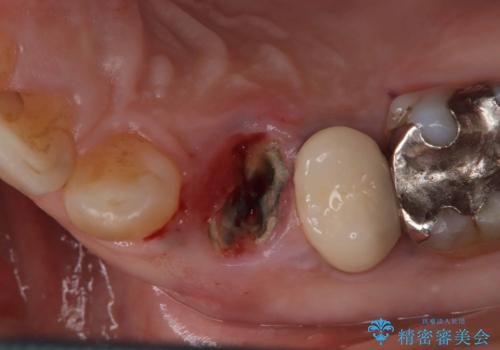

- 「2か月前から歯に違和感があるので診て欲しい」を主訴に来院された患者様です。

被せ物がコア(土台)ごと取れておりかつ根っこも折れてしまっている(歯根破折)状態でした。

歯根破折により保存は不可と診断し抜歯後、骨ができるのを待ってインプラントで治療を行いました。